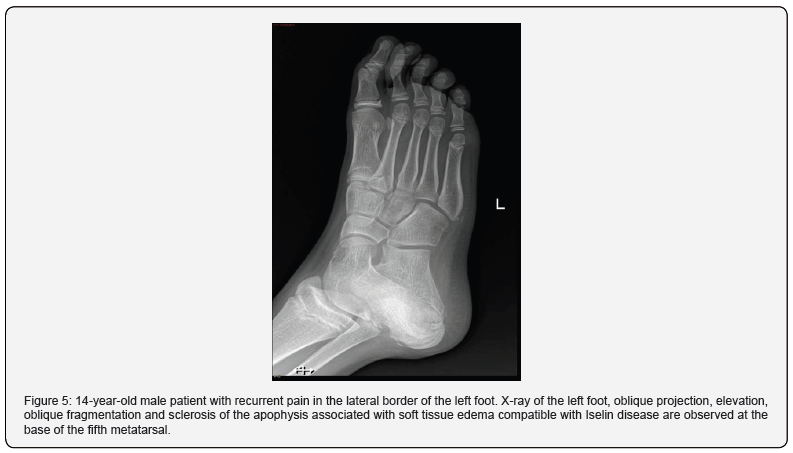

After fractures, we find Iselin Disease or apophysitis (osteochondrosis) of the base of the fifth metatarsal. It was first described in adolescents by Iselin in 1912 called apophysalgia of the ossification nucleus of the base of the 5th metatarsal due to continuous traction of the peroneus brevis muscle. Its main differential diagnosis is avulsion fracture of the styloid process. The oblique projection allows the best visualization of the ossification center, observing morphological irregularity of the ossification nucleus, sclerotic edges without clear fracture lines, there may be separation, and sometimes fragmentation of the apophysis and widening in the region of the growth cartilage (Figure 5). Clinical manifestations include pain on the outer edge of the foot that worsens with activity and improves with rest. Your treatment rest and anti-inflammatory treatment [9].